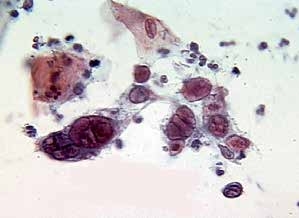

1. 单纯疱疹病毒(herpesvirus simplex)(图2-20~2-24)

图2-20 单纯疱疹病毒(高倍、液基、巴氏染色)

嗜伊红染的核内包涵体(红箭头),形状与其核相似,少见。染色质退变为毛玻璃样(黄箭头)。

图2-21 单纯疱疹病毒(高倍、液基、巴氏染色)

被感染的细胞单核、双核及多核(插图)。核的形态特征:毛玻璃样,拥挤镶嵌,染色质边聚,核膜增厚,有时可见核内包涵体。

细胞形态特征:被感染的细胞表现为多核伴有胞核增大,胞核拥挤镶嵌,毛玻璃样染色质,染色质聚集在核膜下而使核膜增厚,多呈嗜碱性。典型病变细胞特征为:多核、核塑形、染色质边缘化。偶见嗜伊红染色的核内包涵体,形状与其核相似。背景有较明显的急性炎性改变。

疱疹病毒感染不成熟的鳞状上皮细胞、化生细胞以及子宫颈管腺细胞。病毒主要侵犯细胞核,细胞核的变化是诊断的关键。需要注意宫颈细胞学并不是诊断HSV感染最可靠的方法,PCR检测方法相对更敏感和快速。鉴别:炎性的多核柱状上皮、化生细胞、多核巨噬细胞。